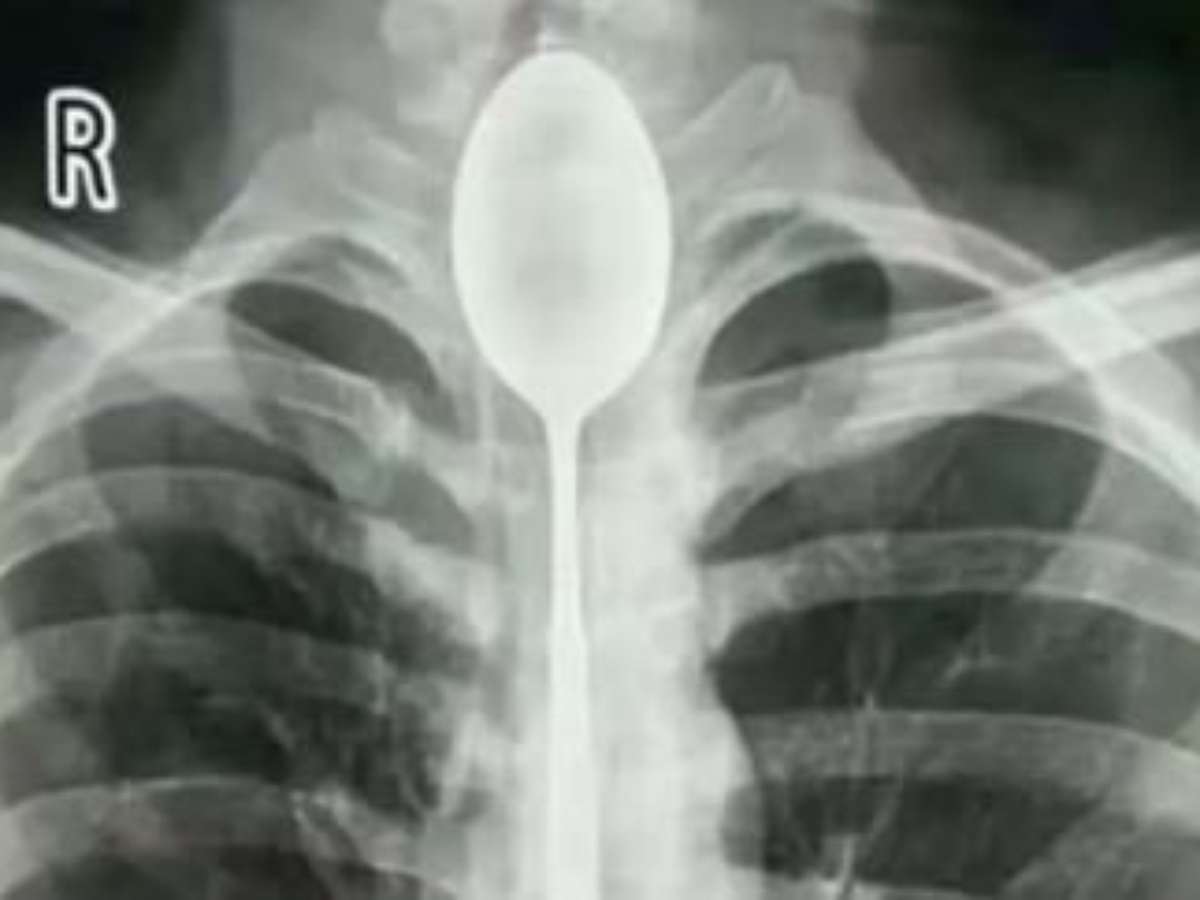

Foto: Divulgação/Xinjiang Meikuang General Hospital

Um chinês, chamado Zhang, engoliu uma colher de aço durante um desafio em 2017. O utensílio de 20 centímetros ficou armazenado no esôfago do rapaz por cerca de um ano e por incrível que pareça, ele não sentiu nenhum desconforto por meses.

Entretanto, em outubro deste ano, o homem começou sentir dores no peito e dificuldades para respirar. Depois de realizar diversos exames, a colher foi identificada na parte superior da faringe até o esôfago de Zhang.

Quando os especialistas averiguaram a garganta do rapaz com um endoscópio, perceberam que a colher estava revestida de muco. "Fiquei muito surpreso. Nunca encontrei um caso semelhante", disse Dr. Yu Xiwu, diretor do Departamento de Otorrinolaringologia do hospital.

A cirurgia para retirar o talher durou duas horas e foi feita no dia 22 de outubro com ajuda de três médicos. Zhang ficou de repouso após o procedimento e foi liberado depois de dois dias.